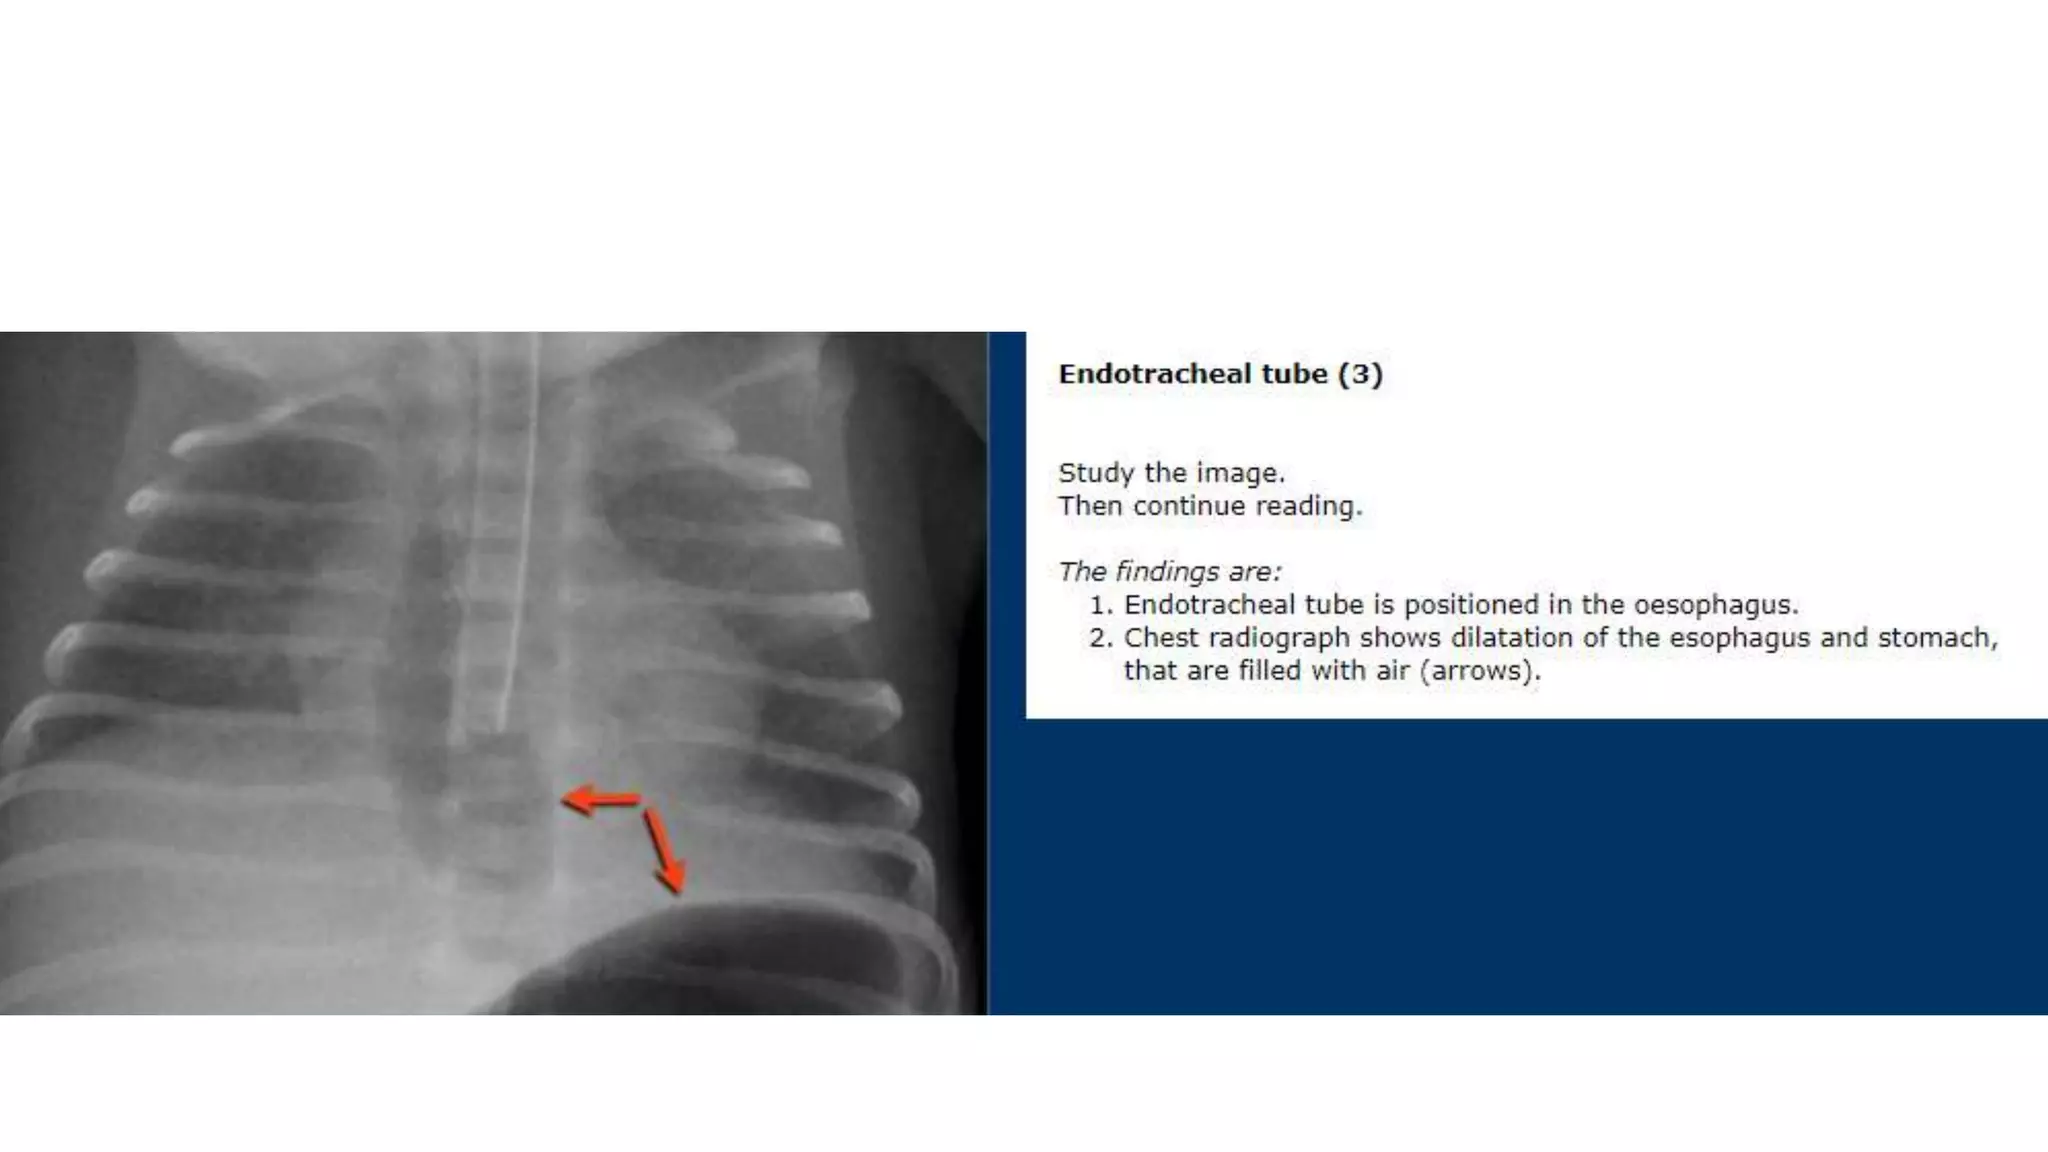

This document provides an overview of neonatal chest x-rays, including when they should and should not be performed, what a normal x-ray looks like, common positions of tubes and catheters, and common causes of respiratory distress in neonates. It discusses the appearance of a normal chest x-ray as well as conditions like respiratory distress syndrome, transient tachypnea of the newborn, meconium aspiration syndrome, and pneumonia. Surgical conditions like diaphragmatic hernia and esophageal atresia are also reviewed.